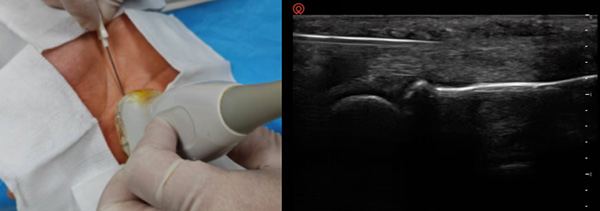

当传统针刀疗法的“松解”精髓,遇上超声实时可视化技术,实现毫米级精准治疗。高频超声如同医生的“眼睛”,清晰呈现肌肉、筋膜、神经、血管的深层结构,全程避开敏感组织,让针刀直达粘连、卡压、炎症的核心靶点,精准剥离挛缩组织、解除神经压迫。创口仅0.4-0.8mm,无需缝合、不留疤痕,治疗后疼痛即刻缓解,随治随走,彻底告别传统“盲探”风险,为腱鞘炎、腕管综合征、肩周炎、钙化性肌腱炎等顽固性疼痛提供微创精准解决方案 。

超声引导下针刀松解及针灸治疗钙化性肌腱炎和肩周炎

超声引导下针刀松解治疗腱鞘炎